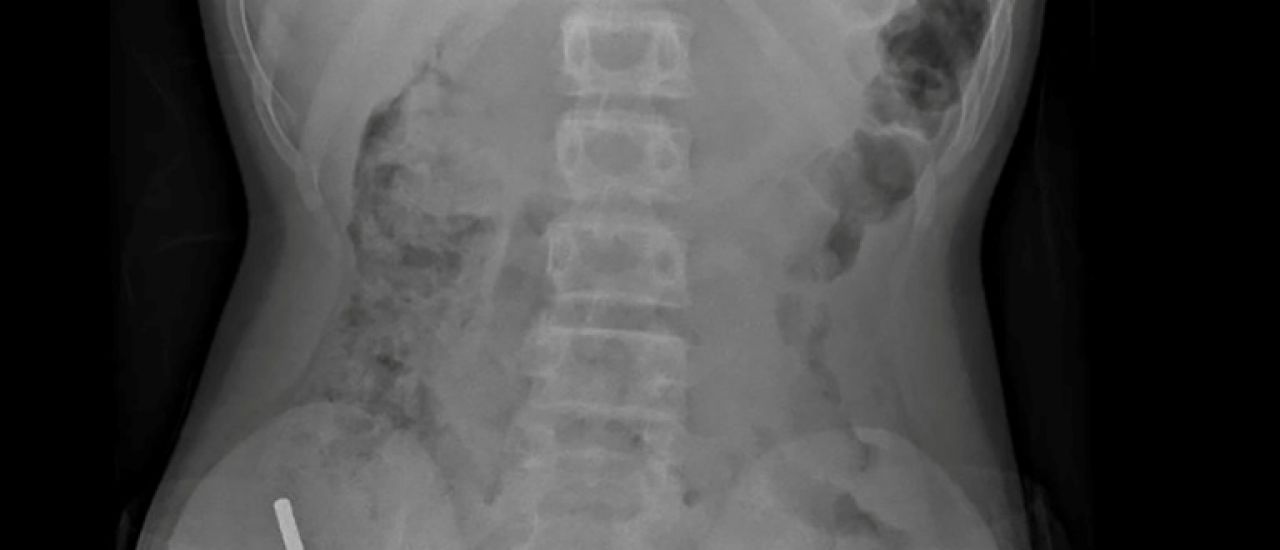

"Il avoué avoir ingéré entre 80 et 100 aimants puissants au néodyme, de 5x2mm environ, une semaine plus tôt", indique un rapport des médecins de l'hôpital de cet hôpital, publié dans le New Zealand Medical Journal (NZMJ).

Les médecins ont déclaré que la pression exercée par les aimants avait provoqué une nécrose dans quatre zones de l'intestin grêle et du gros intestin du garçon.